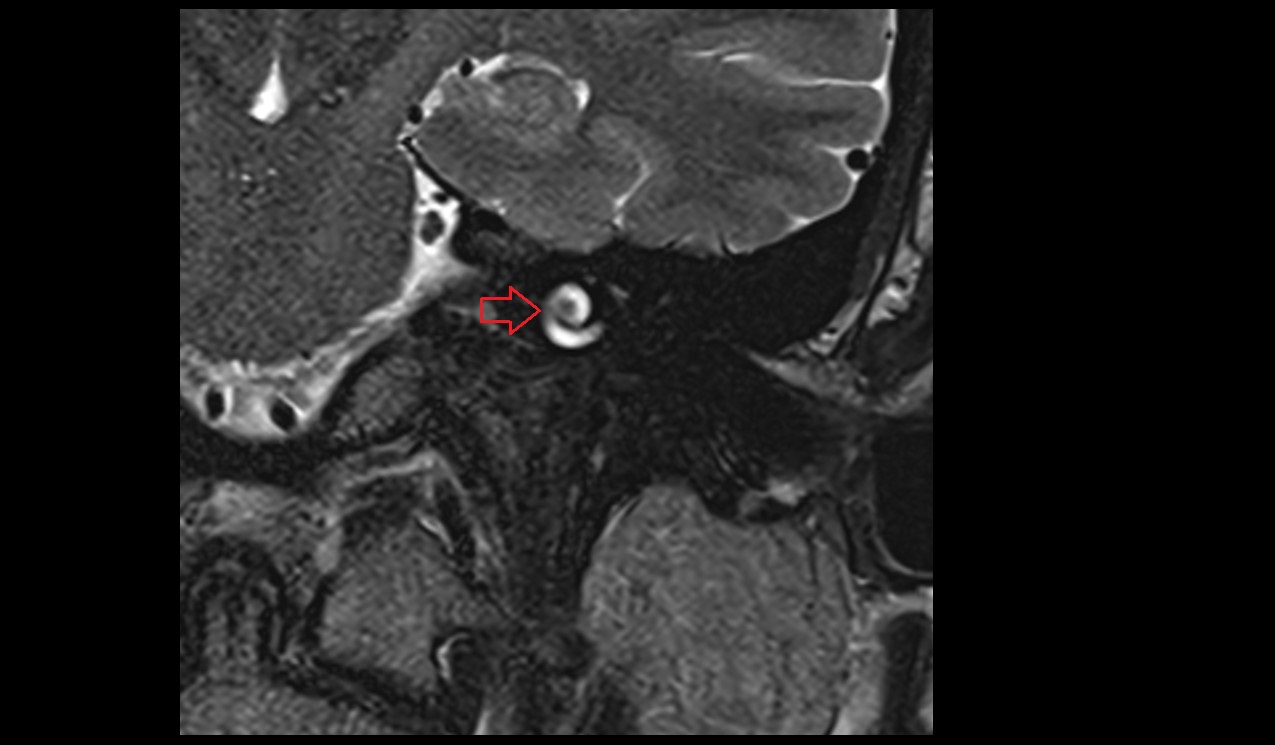

- Mandibular condyle